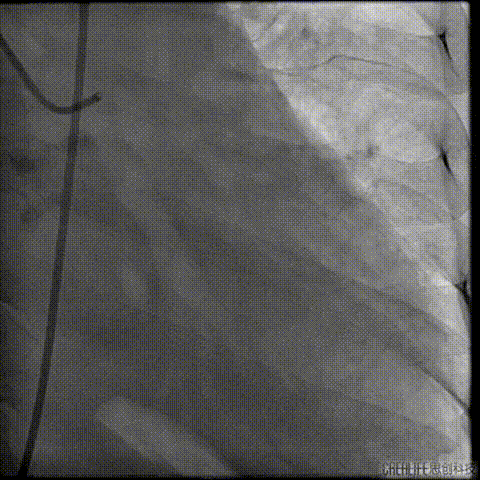

经桡冠脉保护

置入Venus-A32号瓣膜并释放